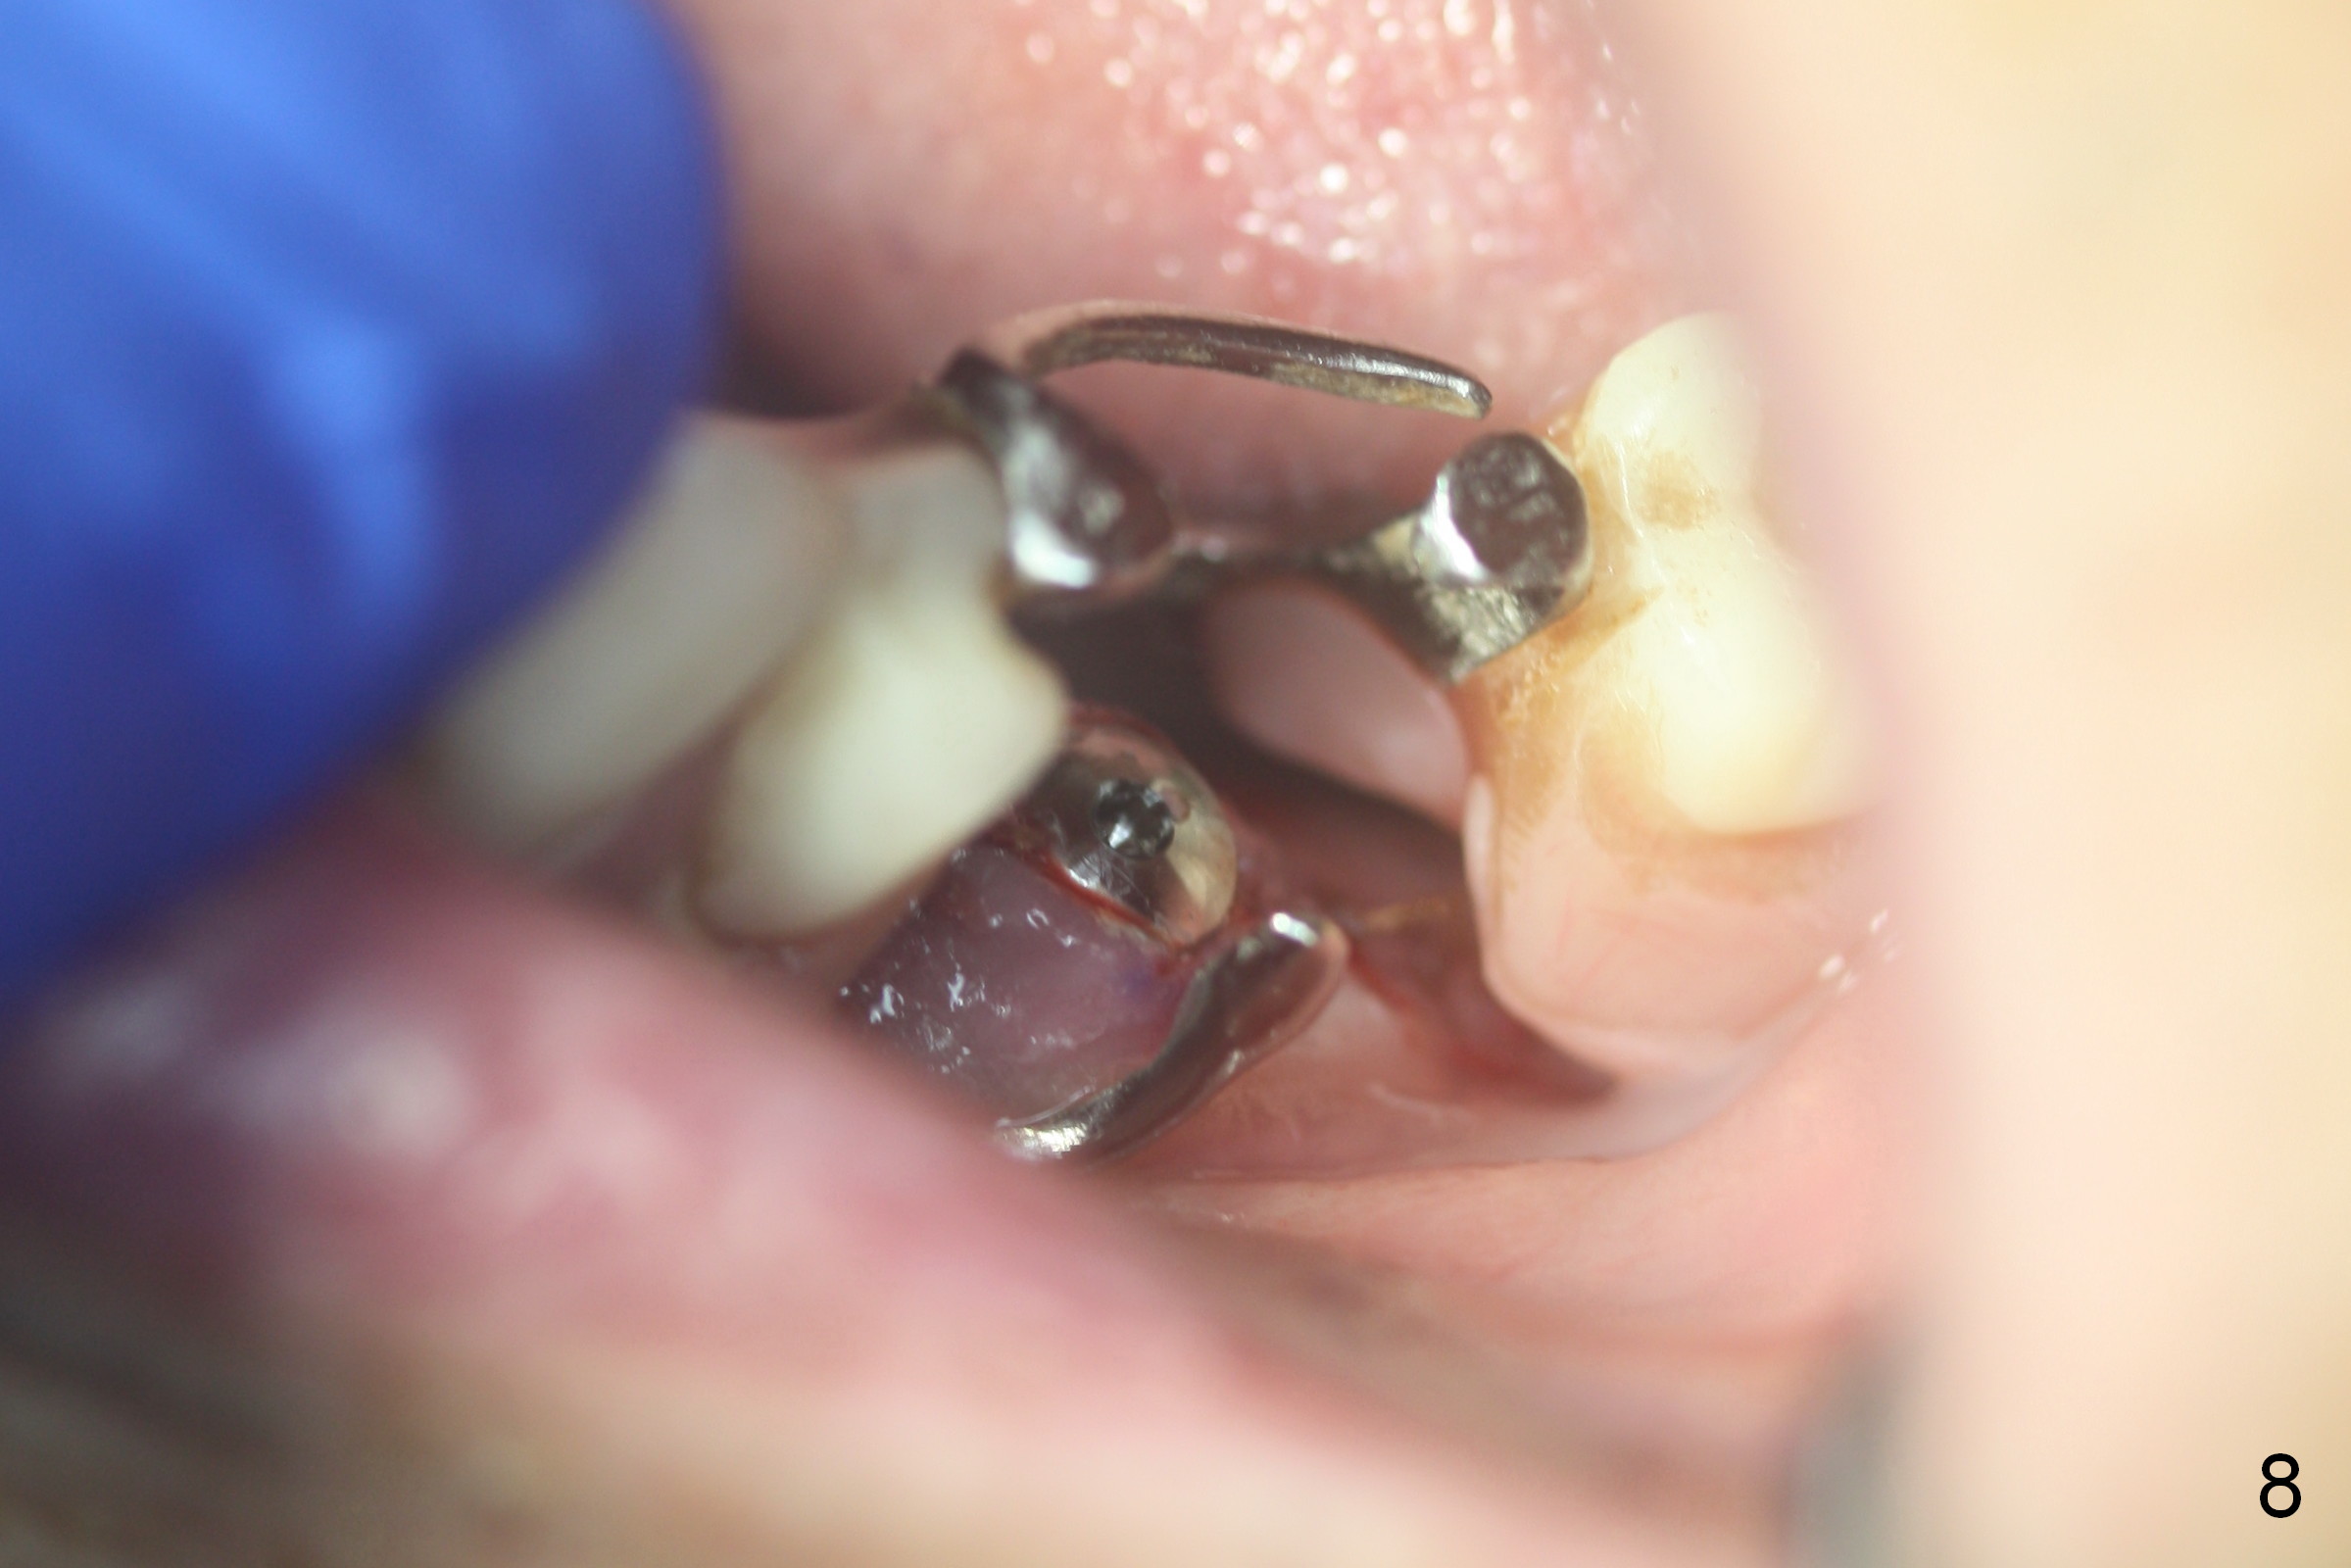

Except the tooth #30, the patient is completely edentulous (Fig.1,2). His chief complaint is "food gets into the missing tooth area". Due to short guide pin (Fig.3) and parallel pin (Fig.4), it is difficult to calculate precisely at the site of #19 the distance to the superior border of the Inferior Alveolar Canal (Fig.4 red dashed line). The clearance appears to be limited when a 4.3 mm drill is in place with 11 mm depth (Fig.5). Therefore an implant shorter than the last drill is placed (5x9 mm, Fig.6). Insertion torque is >50 Ncm. A 5x4(2) mm pair abutment is inserted temporarily to check occlusion with the opposing dentition (A). Finally a 5x2 mm healing abutment is placed with harvested autogenous bone placed between the implant and abutment (Fig.7). Before discharging the patient, the lower RPD is in place to check the position of the implant/abutment (Fig.8).